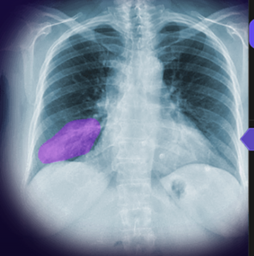

logo.png                                           26-Dec-2024 07:24              100796